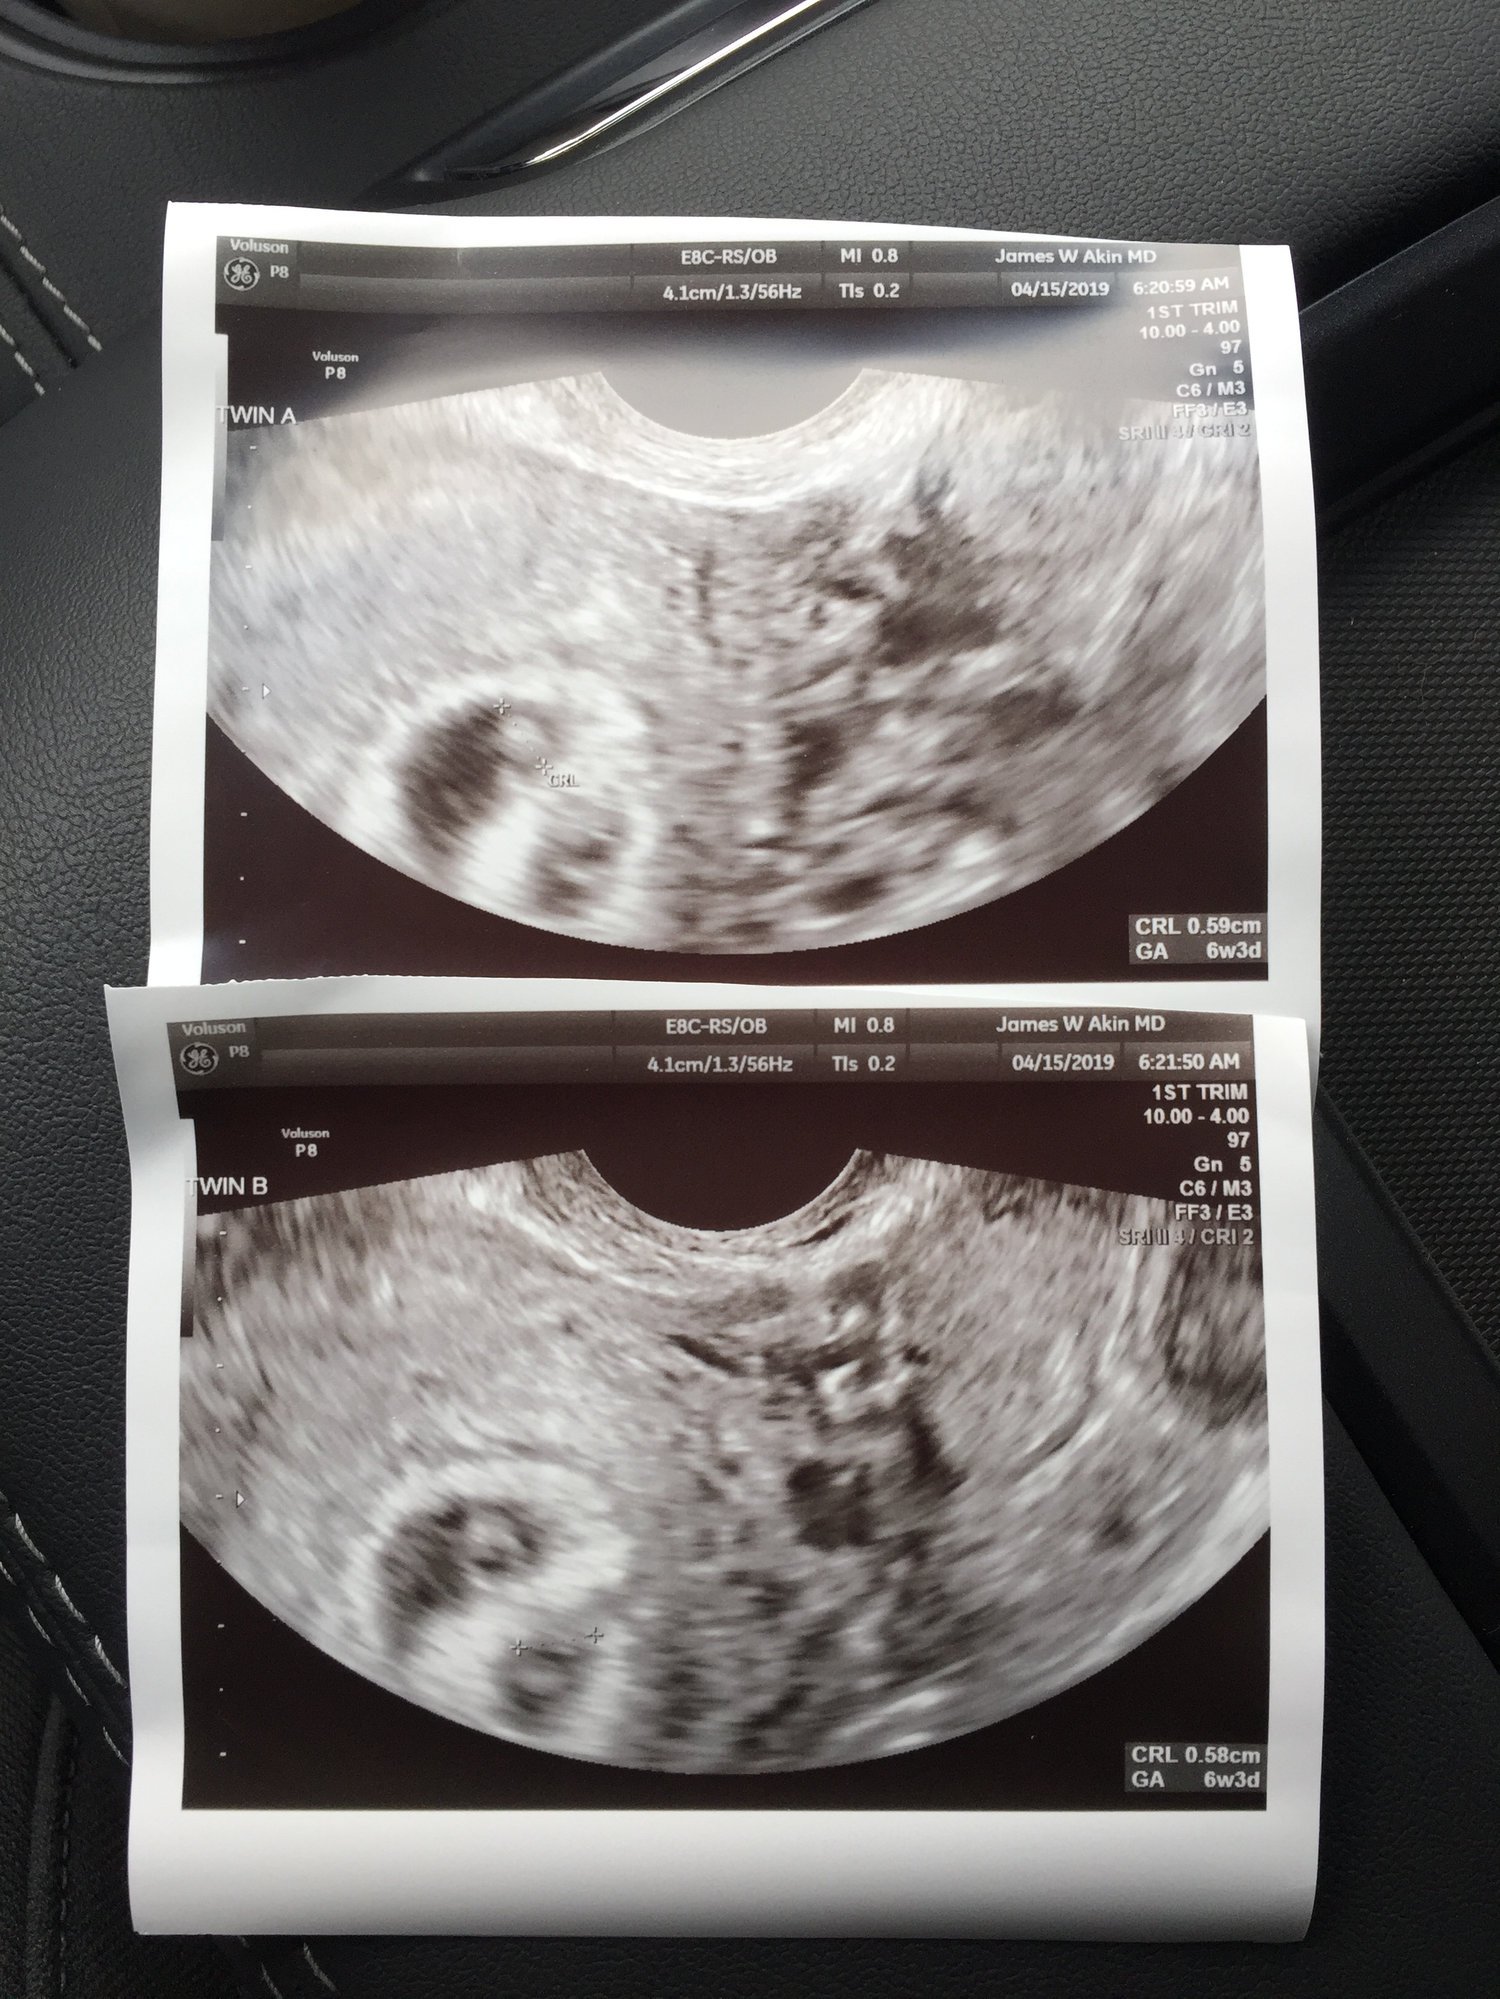

Found out yesterday, I am having twins.. EDD 12.7.19